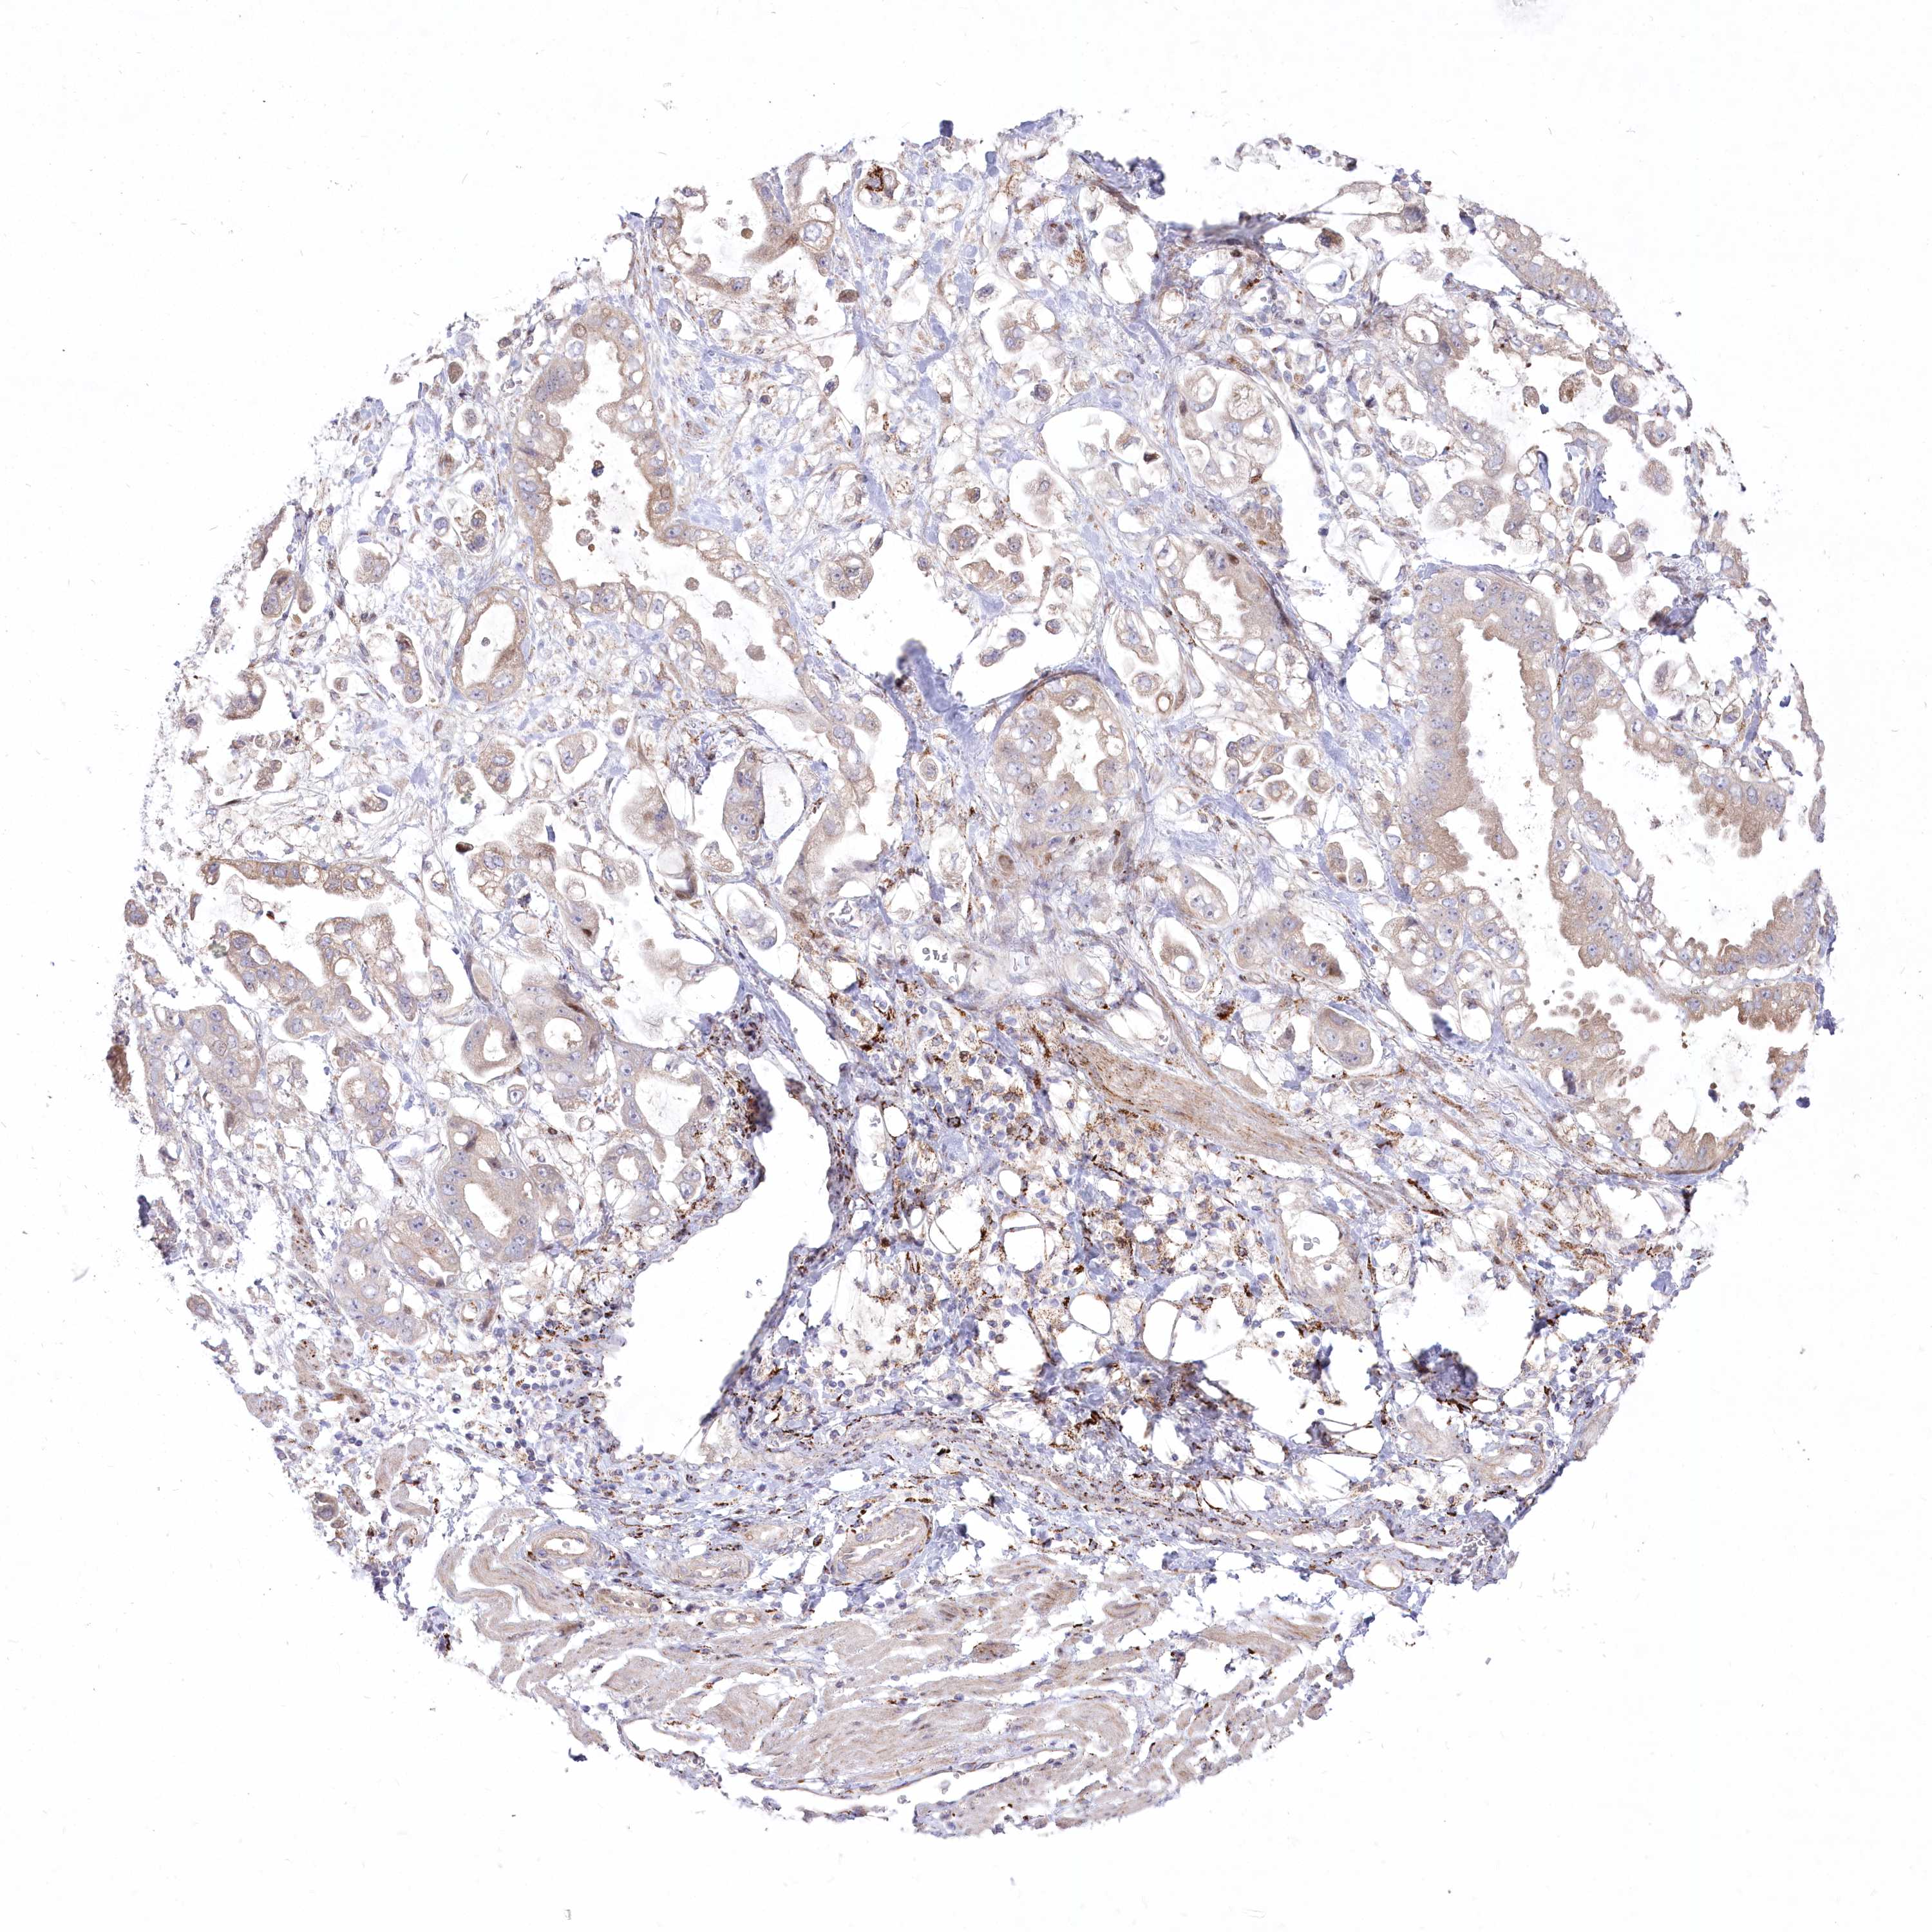

STOMACH CANCER - Protein expressioni

A mouse-over function shows sample information and annotation data. Click on an image to view it in a full screen mode. Samples can be filtered based on level of antibody staining by selecting one or several of the following categories: high, medium, low and not detected. The assay and annotation is described here.

Note that samples used for immunohistochemistry by the Human Protein Atlas do not correspond to samples in the TCGA dataset.

Antibody stainingi

Antibody staining in the annotated cell types in the current human tissue is reported as not detected, low, medium, or high, based on conventional immunohistochemistry profiling in selected tissues. This score is based on the combination of the staining intensity and fraction of stained cells.

Each image is clickable and will lead to virtual microscopy that enables deeper exploration of all samples and also displays staining intensity scores, fraction scores and subcellular localization as well as patient and tissue information for each sample.

Antibody HPA037605

Antibody HPA037606

Staining

High

Medium

Low

Not detected

Intensity

Strong

Moderate

Weak

Negative

Quantity

>75%

75%-25%

<25%

None

Location

Nuclear

Cytoplasmic/membranous

Cytoplasmic/membranous,nuclear

Adenocarcinoma, NOS